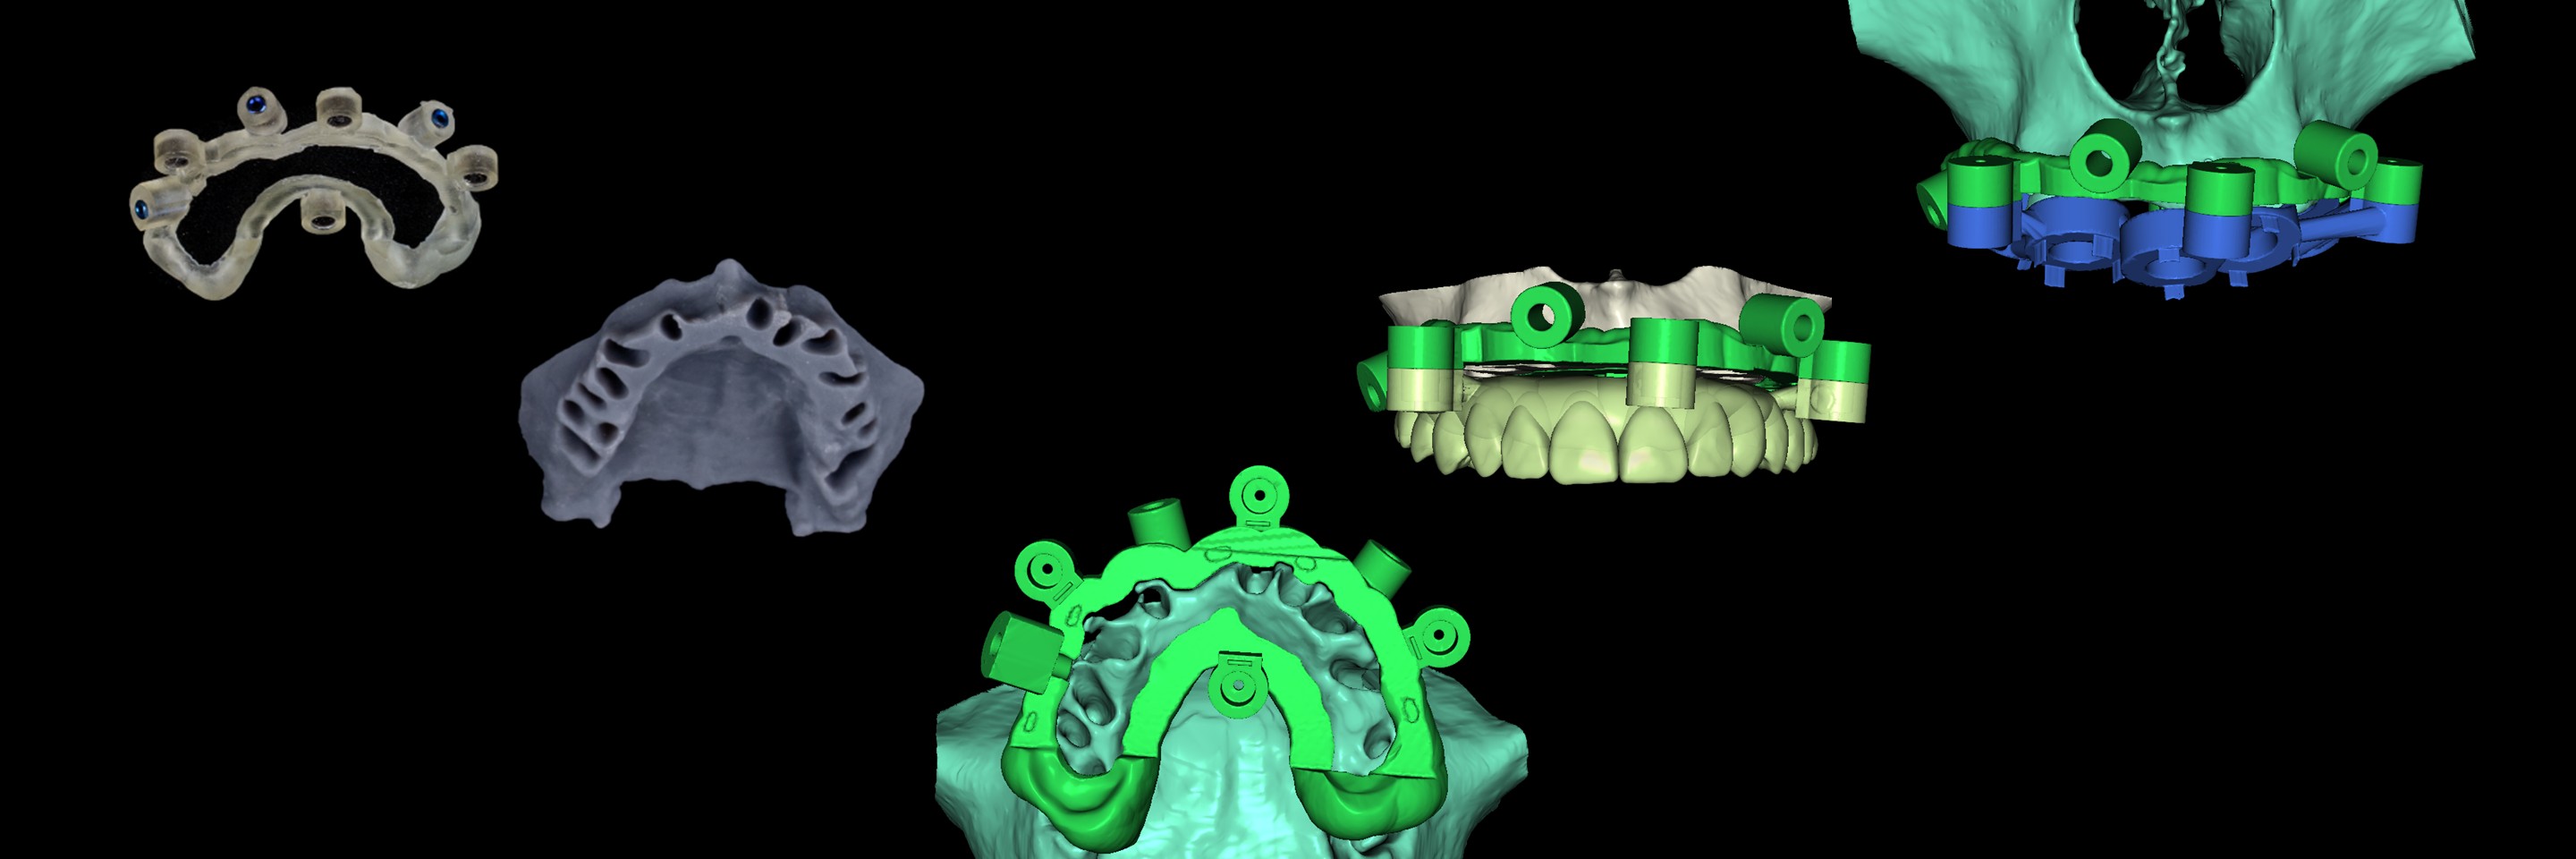

Director’s Clinical Cases

Director’s Clinical Cases